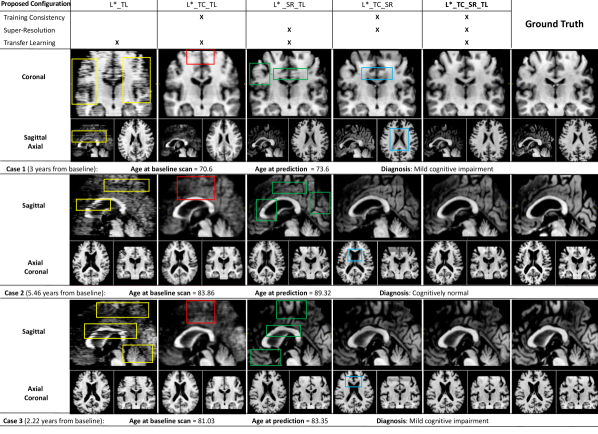

Refer to caption

Figure 6: Qualitative ablation study: Synthetic MRI, generated starting from the baseline scan, for three representative test cases (rows) across different model configurations (columns) involving combinations of training consistency (TC), super-resolution (SR) and transfer learning (TL) blocks on top of the basic model L. Coloured boxes show: spatial discontinuity artefacts (yellow boxes) generated by unstable training; missing anatomical detail (red boxes) when super-resolution is not included; artefacts caused by super-resolution in the presence of spatial discontinuity artefacts (green boxes); and inaccurate morphology (blue boxes) in the ventricles when individualization is omitted from the model.

The configurations of 4D-DANI-Net considered in our ablation studies involve the basic model (denoted by L) obtained by independent training (then stacking together) of MRI slices, plus combinations of the 3D training consistency strategy (denoted by TC and obtained when PWFs are used), the super-resolution block (denoted by SR), and the transfer learning block (denoted by TL). See Section 3 for details of each.

5.3.1 Qualitative Ablation Study

Our qualitative ablation study compared artefacts in synthetic images obtained by different configurations of 4D-DANI-Net for three representative test cases.

Figure 6 shows that the full configuration L_TC_SR_TL produces visually superior synthetic MRI, i.e., fewer artefacts in comparison to synthetic MRI obtained by other configurations. In the approaches lacking 3D consistency constraints (L_TL), the independent training of 2D slice-wise models leads to notable artefacts appearing in sagittal and coronal axes when networks do not converge (yellow boxes in Fig. 6). As intended, such issues are almost eliminated through the use of our 3D training consistency strategy TC (L_TC_TL and L_TC_SR_TL configurations). When TC is used without SR, anatomical details are often not visible (red boxes in Fig. 6) and the images appear overly smooth. Conversely, when SR is used without TC, the super-resolution of artefacts introduces false structures (green boxes in Fig. 6). Disabling the transfer learning procedure TL (configuration L_TC_SR) produces inaccurate morphology, i.e., excessive ventricles expansion, caused by lack of individualization (blue boxes in Fig. 6).